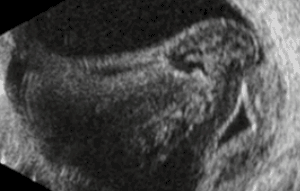

Опухоль сосудистой оболочки и отслойка сетчатки Отслойка сетчатки